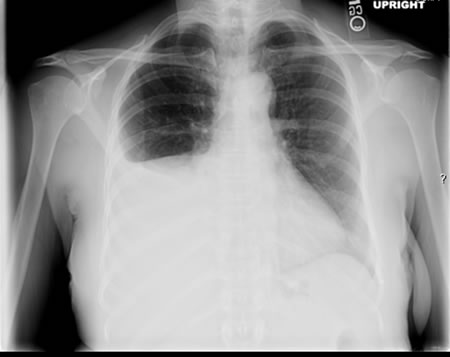

Em indivíduos imunocompetentes é quase sempre anormal. Apresenta-se tipicamente como opacidades fibronodulares nos lobos superiores com ou sem cavitação. O padrão atípico inclui opacidades nos lobos médio e inferior, linfadenopatia hilar ou paratraqueal e/ou derrame pleural.[Figure caption and citation for the preceding image starts]: Tuberculose pulmonar com cavitaçãoDo acervo pessoal de David Horne e do Dr. Masahiro Narita; usado com permissão [Citation ends].